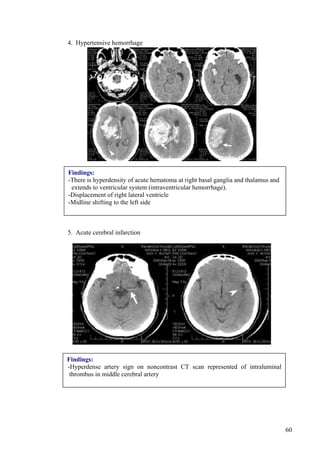

4. Hypertensive hemorrhage

Findings:

-There is hyperdensity of acute hematoma at right basal ganglia and thalamus and

extends to ventricular system (intraventricular hemorrhage).

-Displacement of right lateral ventricle

-Midline shifting to the left side

5. Acute cerebral infarction

-Hyperdense artery sign on noncontrast CT scan represented of intraluminal

thrombus in middle cerebral artery